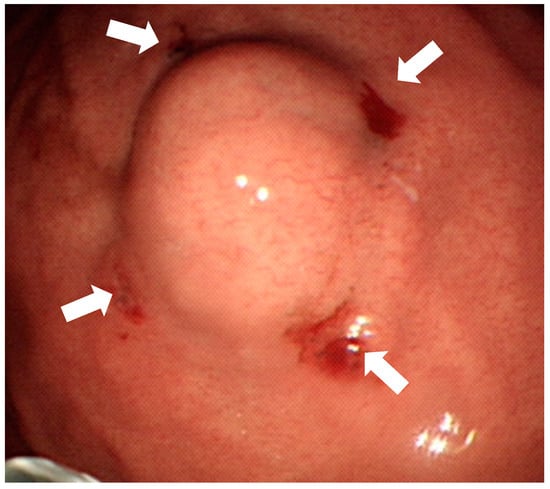

All the procedures were done through totally laparoscopy wedge resection or partial gastrectomy. A four-port technique was briefly used. The initial port was placed through a 2.5-cm infraumbilical incision made using the open method and a commercially available access port (EZ Access; Hakko, Nagano, Japan). During the procedure, a pneumoperitoneum was established using carbon dioxide insufflation at a pressure of approximately 10–12 mmHg according to the body type of the patient. For tumors located away from the pylorus or antrum, we performed a wedge resection using a linear stapler (Ethicon Endo-Surgery, Cincinnati, OH, USA) after dividing the surrounding vessels around the marked area, including tumor with an energy device (LigaSureTM). For the lesion located near the pyloric area, distal gastrectomy (antrectomy) followed by gastrojejunostomy was carried out without omentectomy and lymphadenectomy. The staple line or gastrojejunostomy was reinforced with absorbable suture. One Jackson Pratt drain was placed around the resection site. During laparoscopic gastrectomy, the blue dye was inspected directly from the serosa (Figure 2A). The tumor was then resected along the margin of the tattoo with a stapler smoothly (Figure 2B).

Figure 2.

The tattoo is inspected directly from serosa (white arrows) during laparoscopic surgery without spillage (A) and then the tumor is resected completely (B).